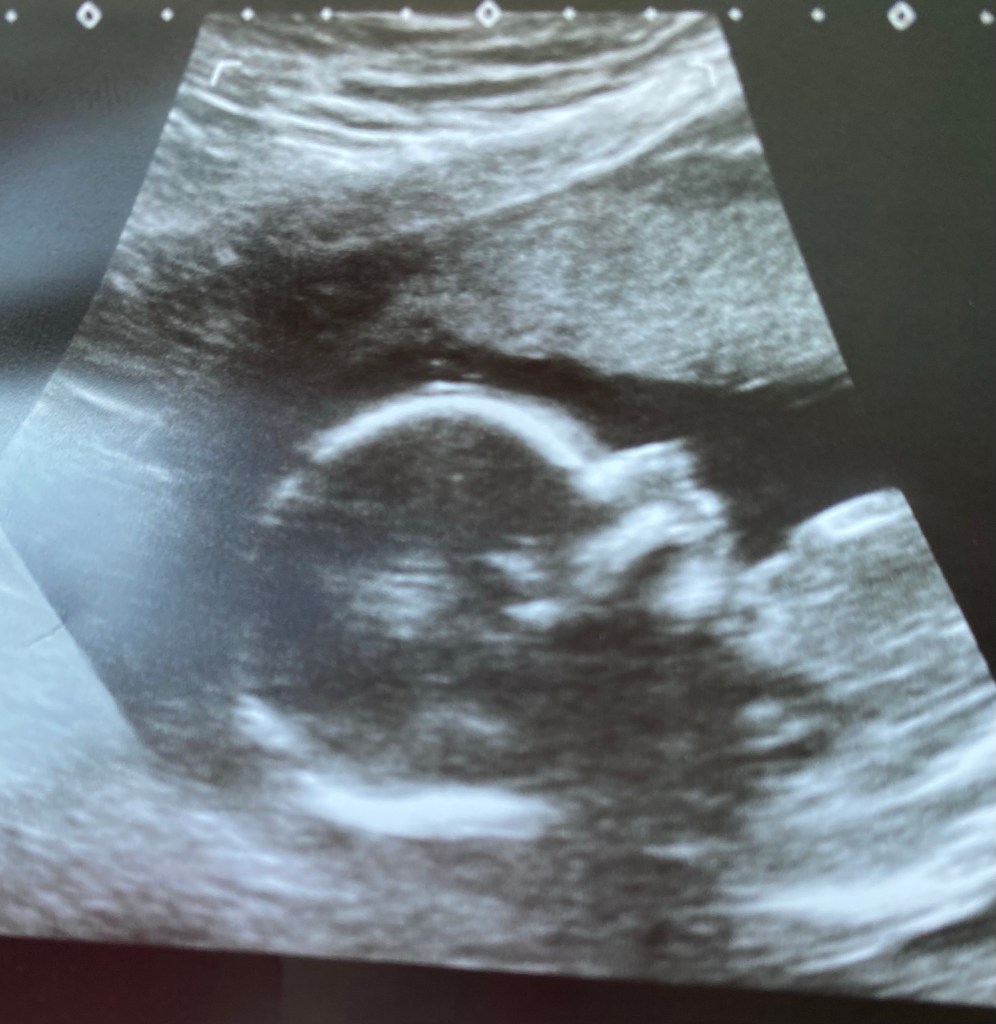

We had another ultrasound of baby Morris this morning.